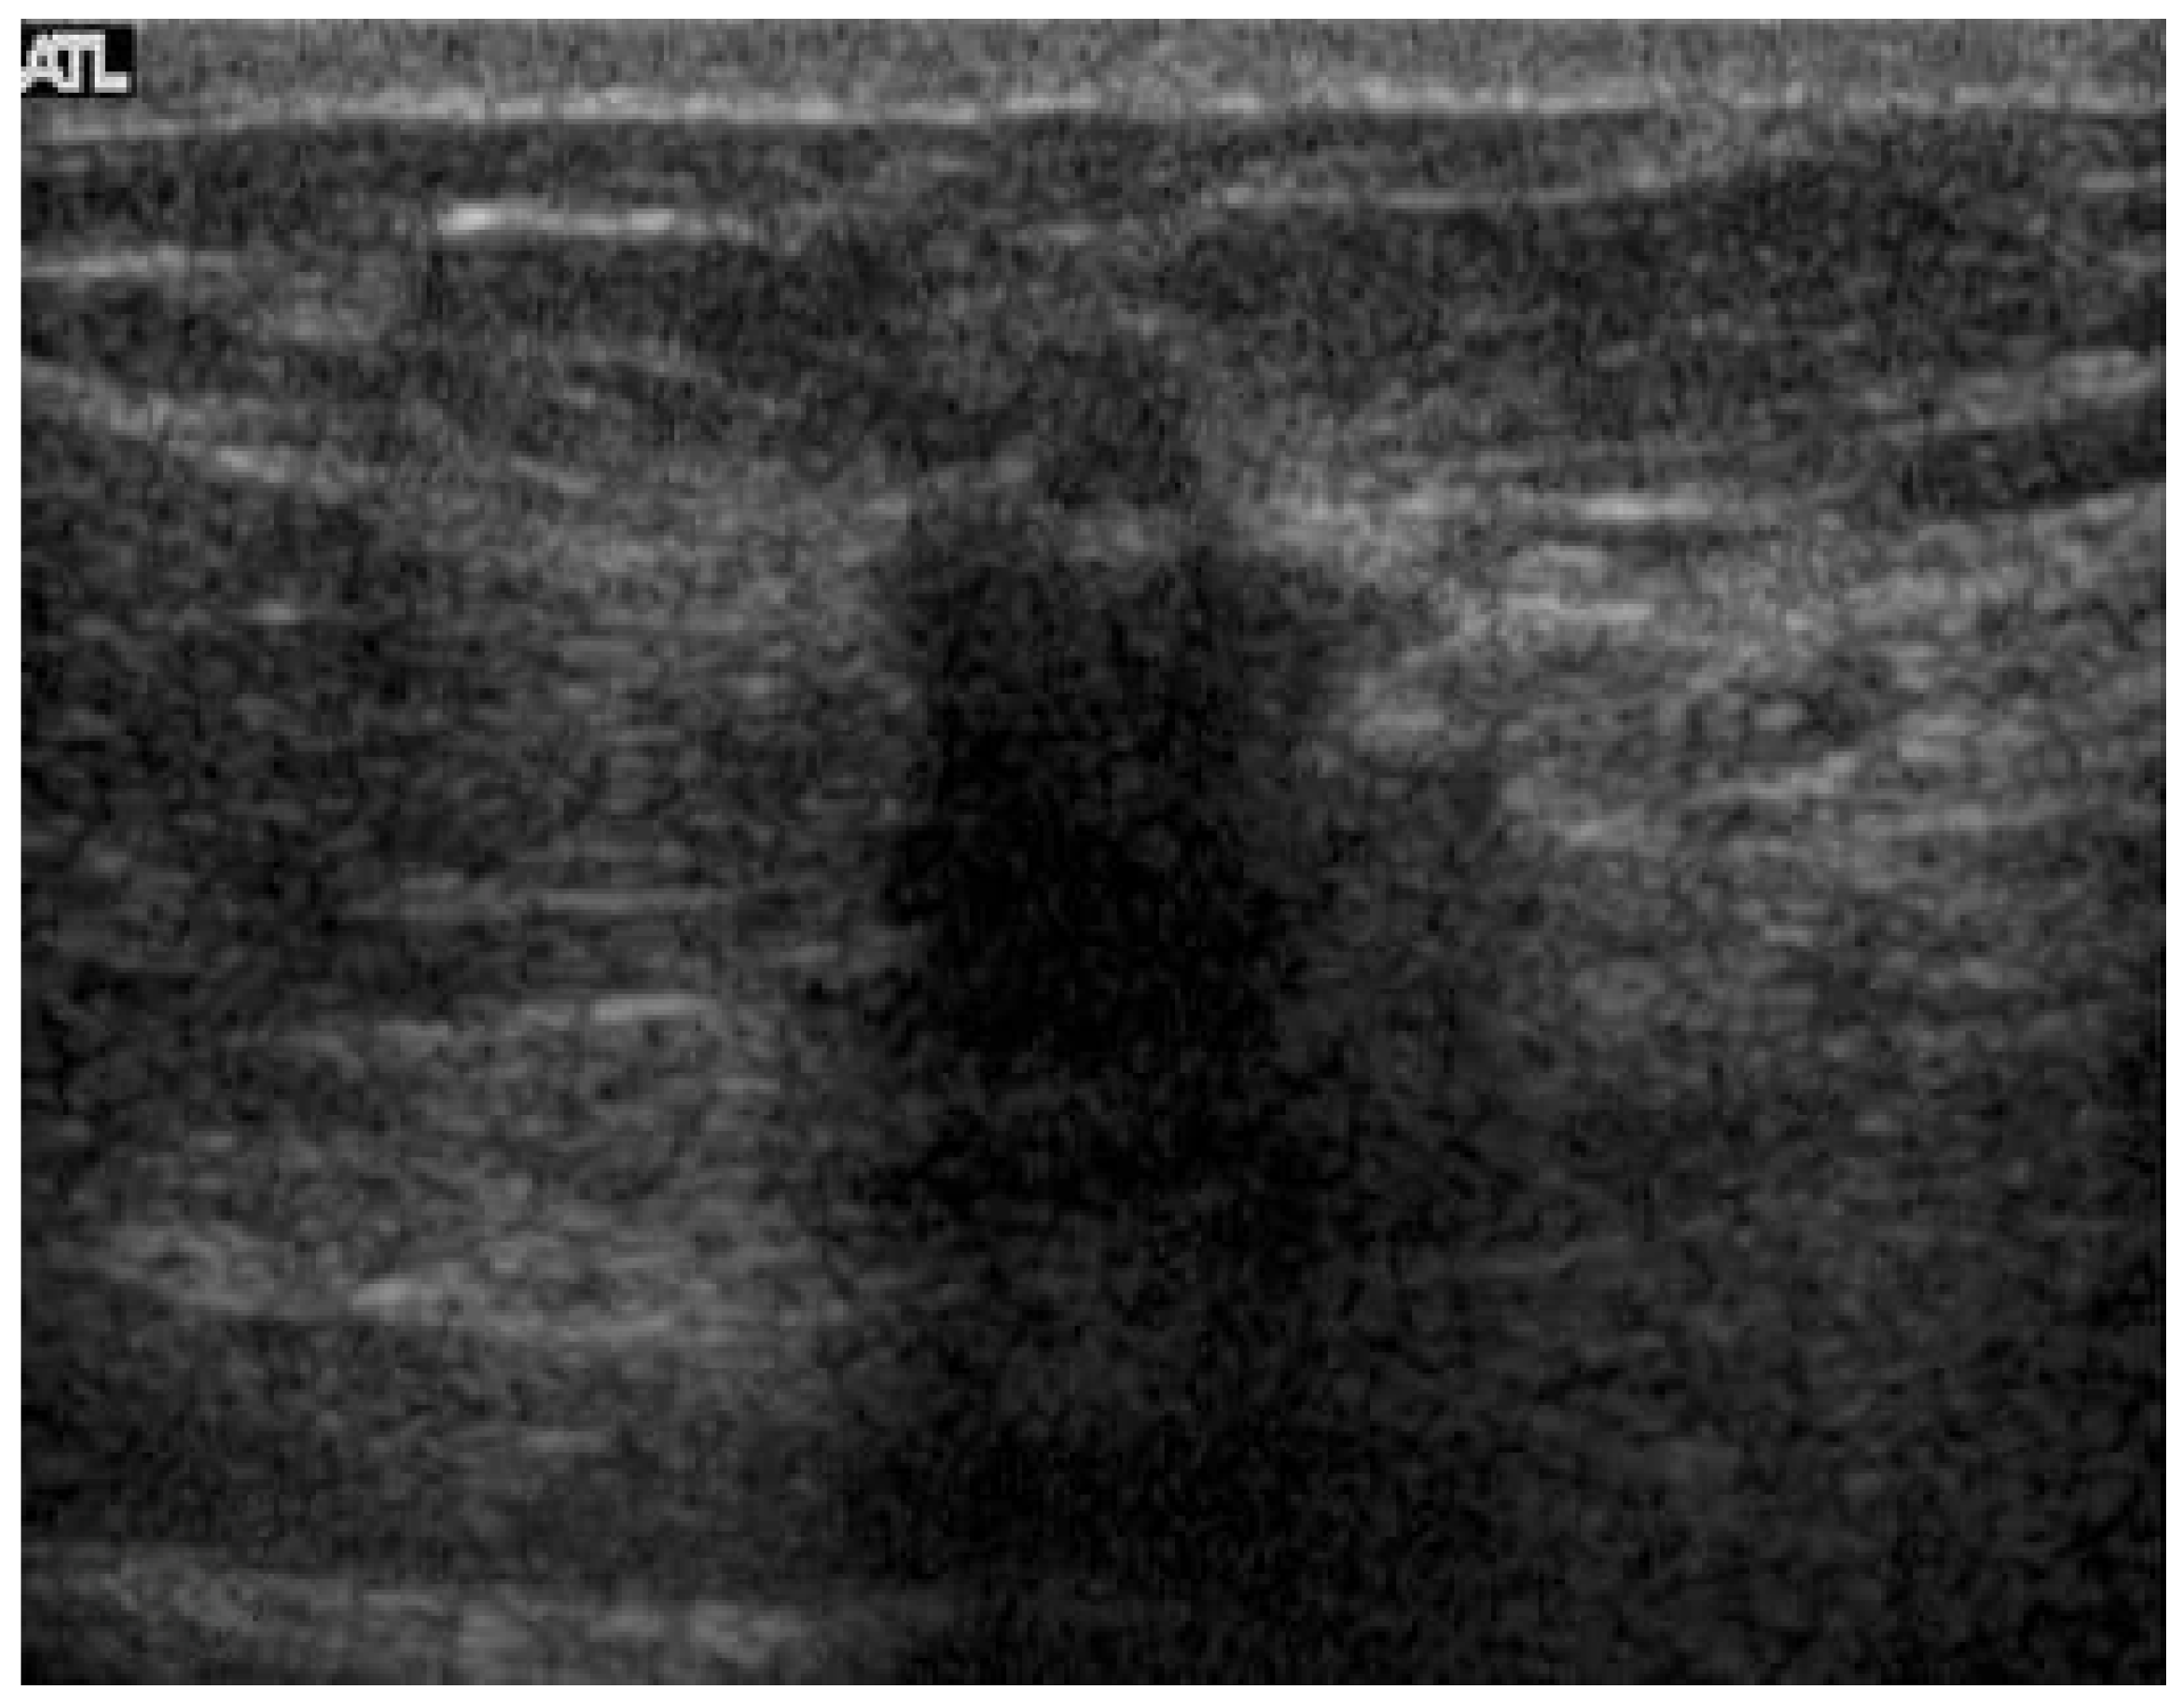

2.2. Ultrasound

- Gokhale, S. Ultrasound characterization of breast masses. Indian J. Radiol. Imaging 2009, 19, 242–247. [Google Scholar] [CrossRef]

- Sehgal, C.; Weinstein, S.; Arger, P.; Conant, E.F. A Review of Breast Ultrasound. J. Mammary Gland Biol. Neoplasia 2006, 11, 113–123. [Google Scholar] [CrossRef] [PubMed]